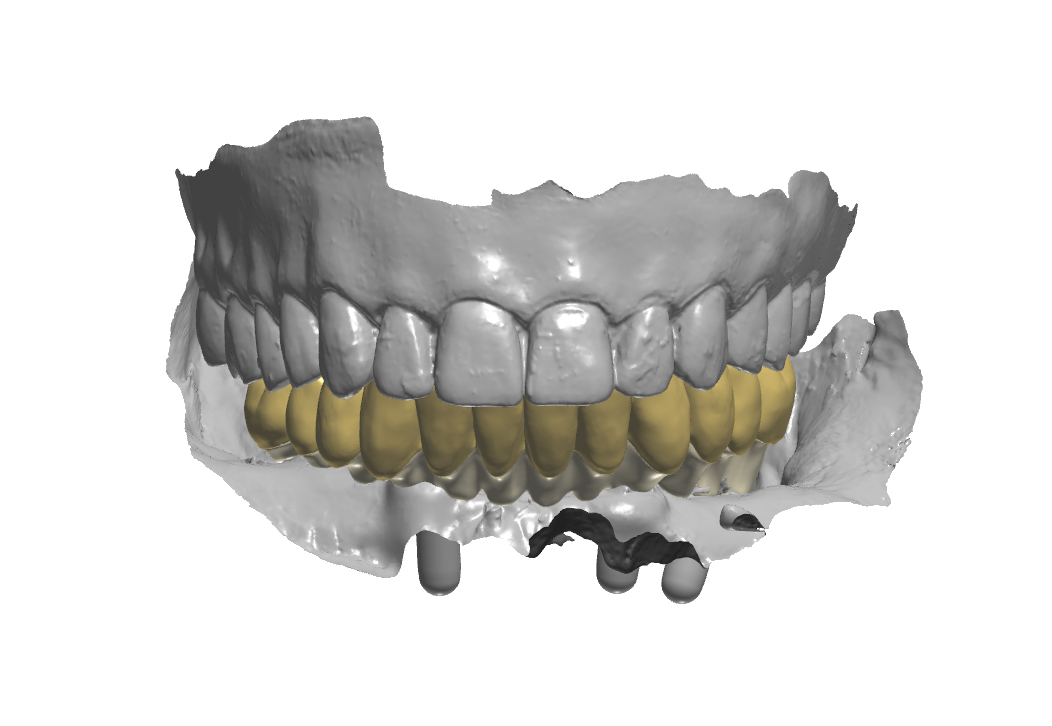

Arcate scansionate all’interno dell’articolatore digitale

Fig. 8. (b) Arcate scansionate all’interno dell’articolatore digitale, in evidenza gli ScanSke.

Prospettiva frontale della protesi progettata

Fig. 9. (a) Prospettiva frontale della protesi progettata in base all’occlusione abituale della paziente

Prospettiva dall’alto della protesi inferiore

Fig. 9. (b) Prospettiva dall’alto della protesi inferiore, in evidenza gli Scan Ske.

Prospettiva laterale sinistra della protesi in occlusione

Fig. 9. (c) Prospettiva laterale sinistra della protesi in occlusione, in evidenza gli ScanSke.